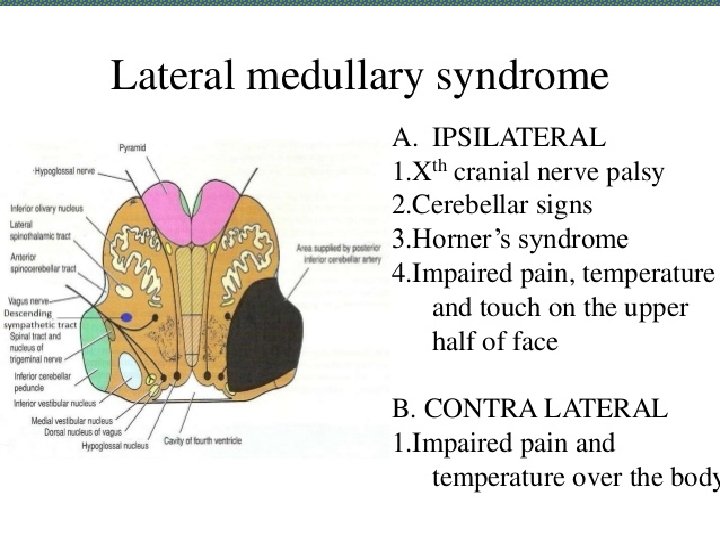

Localization of Lesion Midbrain: CROSSED HEMIPLEGIA: Ø 3 rd /4 th CN are involved on one side and hemiplegia of opposite side Pons: Ø 5 th, 6 th, 7 th and 8 th CN nuclei are present in pons. Ø One or more of these CNs are paralyzed on one side and hemiplegia is on the other side. Ø Pupils are pinpoint but reactive to light Ø Hyperpyrexia may be present Medulla Oblongata: Ø 9 th, 10 th, 11 th and 12 th CN nuclei are present in medulla. Ø One or more of these CNs are paralyzed on one side and hemiplegia is on the other side.

LATERAL MEDULLARY SYNDROME • Also called posterior inferior cerebellar artery (PICA) thrombosis and Wallenberg’s syndrome) • Acommon example of brainstem infarction presenting as acute vertigo with cerebellar and other signs. It follows • Thromboembolism in the PICA or its branches, vertebral artery thromboembolism or dissection. • Features depend on the precise structures damaged. MEDIAL MEDULLARY SYNDROME • Characterized by a set of clinical features resulting from occlusion of the anterior spinal artery. This results in the infarction of medial part of the medulla oblongata.